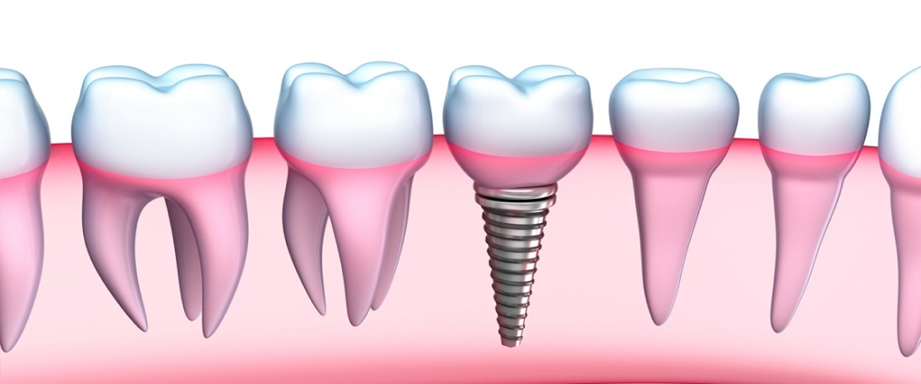

Reemplazamos la pieza dental original por una fabricada en Titanio biocompatible que se introduce en el hueso de la mandíbula, sobre ésta nueva raíz se fija una pieza de metal y cerámica (corona) resistente que se iguala en color y forma con el fin de brindar un aspecto lo más natural posible.

- El implante se fusiona con el hueso mandibular, proporcionando un soporte estable para los dientes artificiales

- (Si le falta un diente)

- Implante fabricado en Titanio Grado V de la más alta pureza.

- Reemplaza la raíz del diente y evita la perdida de hueso.

- Indicado para adultos y tercera edad.

- Respaldo casa de implantes SIN